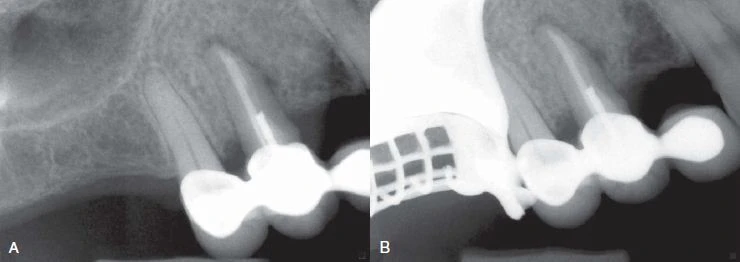

Đôi lúc nứt dọc chân răng hoặc chia chân răng có thể chẩn đoán rõ ràng bằng X quang. Tuy nhiên, hầu hết trường hợp đường nứt nằm trên một mặt phẳng và không nhận ra được trên X quang. Trong một nghiên cứu ở những răng đã được nhổ, các nhà nghiên cứu cho rằng sẽ thấy được vết nứt khi tia X được chiếu trong vòng 4 độ đối với mặt phẳng nứt. Nếu nằm ngoài góc này thì không thấy rõ được đường nứt. Họ cũng nhận thấy rằng nếu có nứt dọc thì chúng chỉ thấy được trên X quang trong 35.7% trường hợp.

Hình 10. Nứt dọc chân răng dẫn đến chia đôi chân răng, điều này có thể phát hiện dược trên X quang

Hình 11. Mặc dù nứt dọc chân răng không phải lúc nào cũng thấy được trên X quang nhưng với một góc chụp đúng thì có thể quan sát rõ đường nứt.

Đường xi măng

Nứt dọc chân răng hoặc chia chân răng có thể mở rộng thừ mặt gần đến mặt xa của răng, thường đường nứt này xảy ra sau khi thực hiện điều trị nội nha. Đôi lúc sẽ thấy một hình ảnh “đường xi măng” dọc hoặc băng ngang qua chân răng. Phần xi măng bị đẩy qua đường nứt, sau đó có thể thấy được trên X quang. Nha sĩ có thể nhầm với hình ảnh phần xi măng bị đẩy qua ống tuỷ phụ, nhưng trong trường hợp nứt răng thì phần xi măng sẽ bị đẩy ra khuêch tán hơn và không có hình ảnh ống tuỷ bên đổ ra từ ống tuỷ chính.

Hình 12. Hình ảnh “đường xi măng”